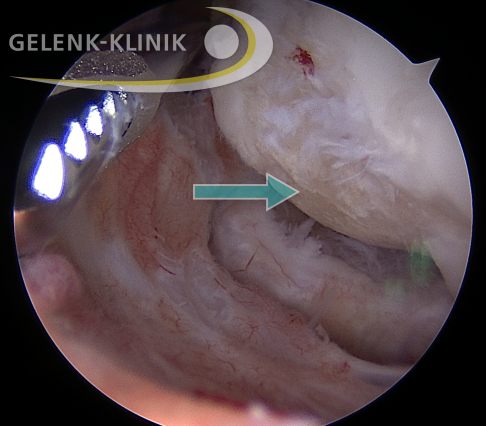

Für das Ellenbogengelenk steht die minimalinvasive Gelenkspiegelung (Arthroskopie) zur Verfügung, um die Beschaffenheit des Gelenks zu untersuchen und während des gleichen Eingriffs zu behandeln.

Dabei kann der Operateur freie Gekenkkörper entfernen oder die Gelenkflächen reinigen oder geschädigtes Gewebe abtragen (Debridement).

Stellt sich bei der Arthroskopie heraus, dass es sich um einen örtlich begrenzten, sogenannten fokalen Knorpelschaden handelt, kann der behandelnde Spezialist auch die Möglichkeit einer Knorpelregeneration in Erwägung ziehen. Insbesondere am Kniegelenk wenden die Spezialisten der Gelenk-Klinik regelmäßig Verfahren wie die autologen Knorpelzelltransplantation, Minced Cartilagen oder zellfreie Membranen an. Am Ellenbogengelenk hat sich aufgrund der häufig eher kleineren Defekte die reine Mikrofrakturierung bewährt, so dass den genannten Verfahren am Ellenbogengelenk Seltenheitswert zu kommt.